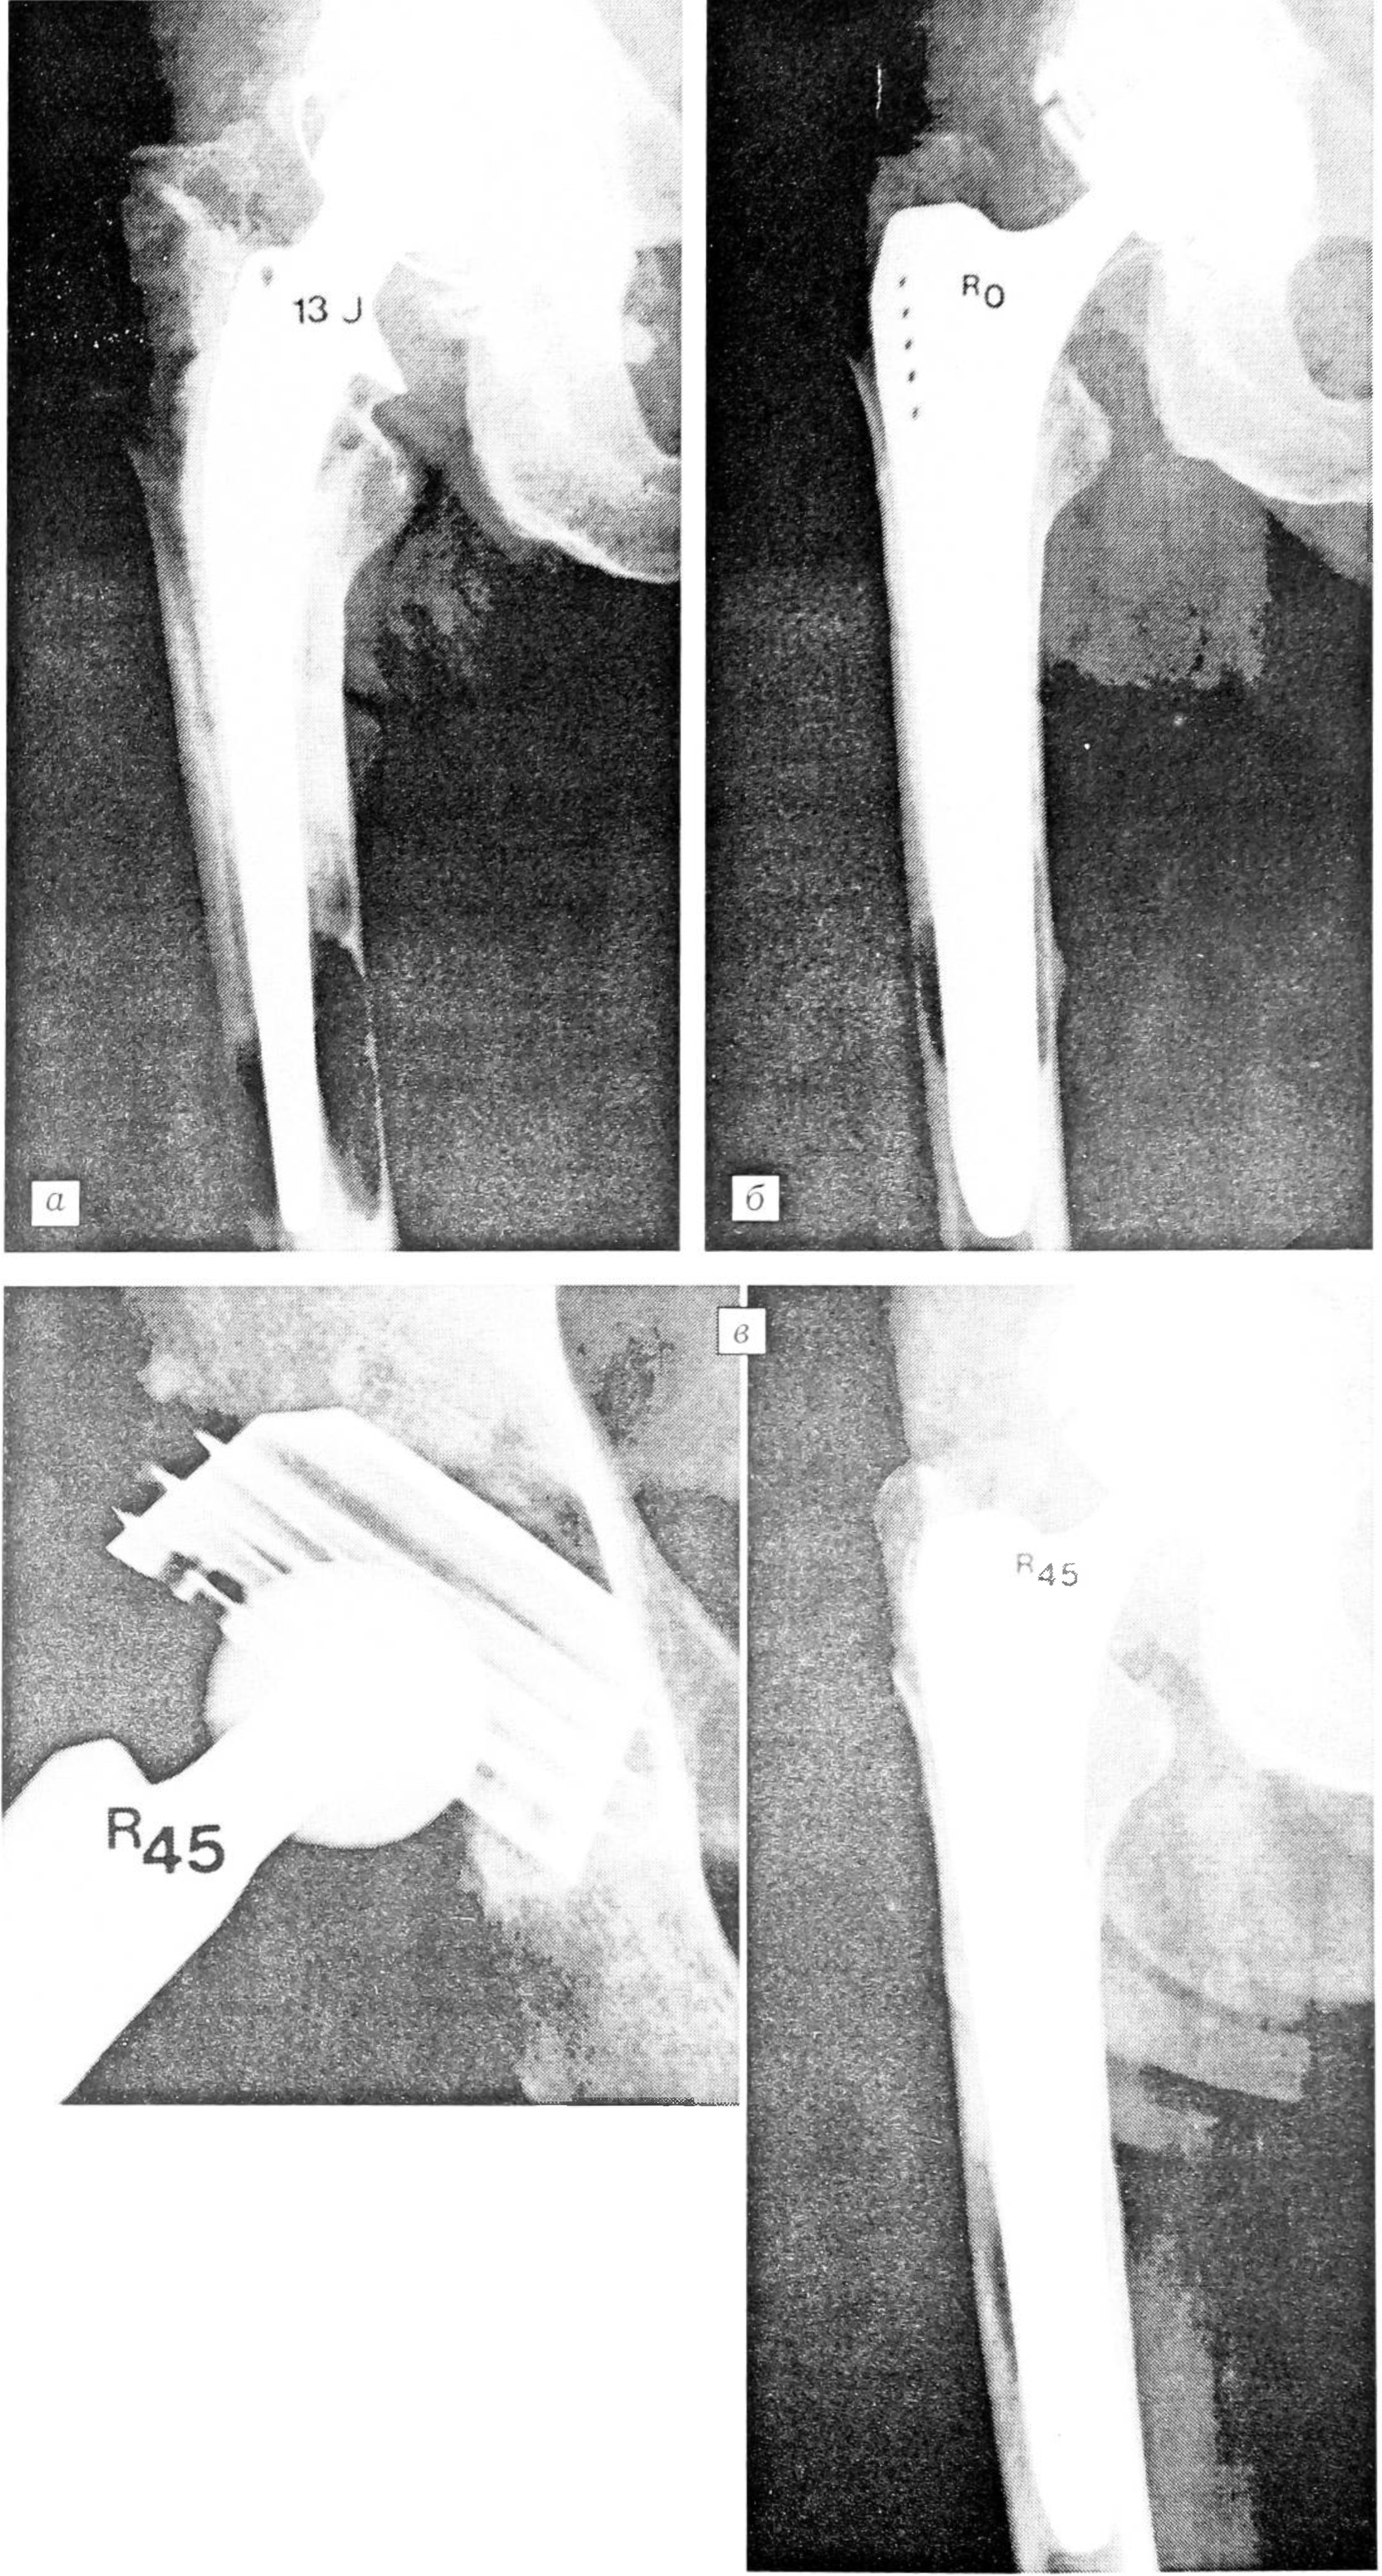

Рис. 2.

а — через 13 лет после первичного тотального бесцементного эндопротезирования тазобедренного сустава: выраженная потеря костной ткани, нестабильность и смещение ножки эндопротеза (Engelbrecht 3);

б — непосредственно после повторного тотального эндопротезирования (чашка Zweymuller, ножка SLR-Plus);

в — через 50 мес после повторного эндопротезирования: хорошая костная интеграция вокруг компонентов эндопротеза.

Рис. 3.

а — через 13 лет после первичного тотального бесцементного эндопротезирования тазобедренного сустава: выраженный кортикальный дефект в зоне дистальной трети ножки;

б — непосредственно после повторного тотального бесцементного эндопротезирования (чашка Bicon Zweymuller, ножка SLR-Plus);

в — через 45 мес после повторного эндопротезирования: хорошая костная интеграция вокруг компонентов эндопротеза.